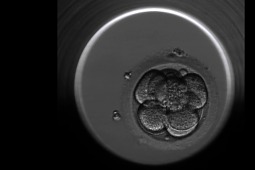

Embrioskop to innowacyjny inkubator zarodków, wyposażony w zintegrowane, specjalistyczne kamery, umożliwiające ciągły monitoring zapłodnionych komórek. Pozwala to na kompleksową ocenę potencjału i rozwoju zarodków w czasie inkubacji przed transferem do macicy, bez narażania ich na działanie czynników zewnętrznych.

Po umieszczeniu zapłodnionych komórek w embrioskopie, urządzenie wykonuje w sposób ciągły i automatyczny zdjęcia poszczególnych oocytów, zygot oraz zarodków z częstotliwością ok. 15 minut. System jest nieustannie kontrolowany przez komputer, gdzie zbierane są pliki ze zdjęciami. Embriolog obserwuje jedynie film poklatkowy złożony z sekwencji obrazów w komputerze. Na podstawie jego analizy ocenia aktualne cechy i tempo rozwoju zarodka, dynamikę podziałów komórkowych oraz czas ich trwania. Zastosowanie tego typu obserwacji jest pomocne w każdym przypadku, ze szczególnym naciskiem na pary, u których zapładniana jest większa ilość komórek, a ich inkubacja trwa do 5 dób (stadium blastocysty).